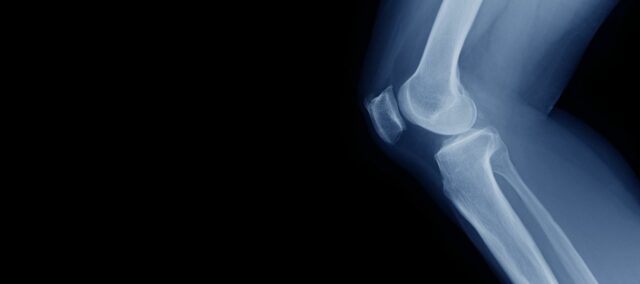

Kuadriseps gücünün diz kıkırdağı üzerindeki etkisi

Optimal kuadriseps gücü, günlük yaşamda iyi diz fonksiyonu için gereklidir. Kuadriseps kası önemli bir dengeleyici ve şok emici olduğundan, dizin eklem yüzeyindeki yüklerin dağıtılmasına yardımcı olur. Bu, özellikle yaşlanan nüfus ve obezite hastalarının sayısındaki artış göz önüne alındığında çok önemlidir. Şu anda diz osteoartritinin (OA) gerçek bir tedavisi olmadığından, OA'ya ilerlemeyi yavaşlatmak veya mümkünse başlamasını önlemek çok önemlidir. Bu nedenle, diz OA'sında güçlendirme ilk basamak tedavi olarak savunulmaktadır. Şimdiye kadar, kuadriseps gücünün diz kıkırdağı üzerindeki etkisi için kesin sonuçlar çıkarılamamıştır. İşte bu çalışma burada devreye giriyor.